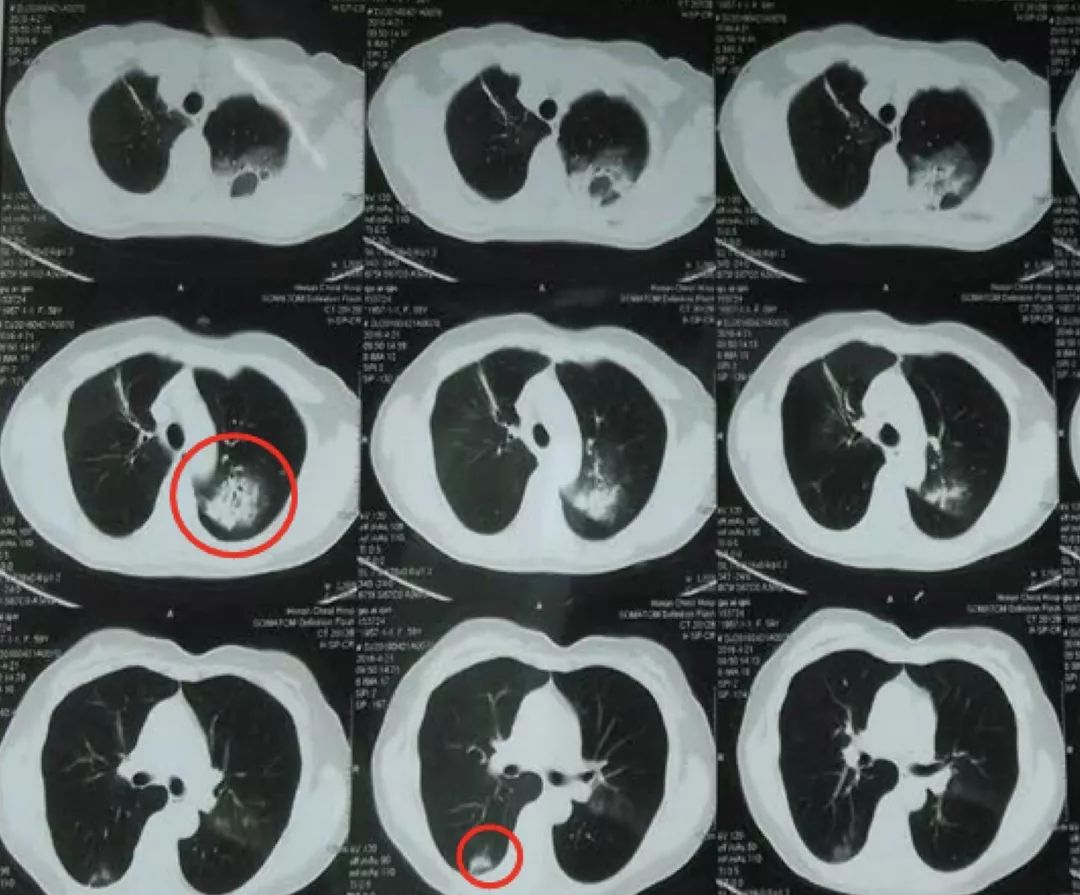

经过抗感染治疗7天,患者体温正常,咳嗽、咳痰好转,间断胸闷,查体 :左上肺语颤稍增强,叩诊浊音,左上肺呼吸音粗,未闻及干、湿罗音。但2017-3-12复查胸部CT,左上肺及右下肺背段病灶无明显吸收。

2017-3-12胸部CT:

2017-3-5胸部CT右上肺大片状高密度影消散,仅留下少许高密度条索影,但左肺上叶后段出现新发病变,但与之前右肺上叶病变影像学特征有所不同,之前三次影像学病灶密度是比较均匀的,此次左肺上叶后段病变,除了实变之外可见类空洞样改变,仍有支气管充气征,周围见细条索影,右下肺背段见类结节影像。

2017-1-23病灶呈楔形改变,还要与急性肺栓塞引起的肺梗死相鉴别,但病变过程及临床检查不支持。影像角度来讲,病灶的游走性是指另一部位发生与该部位同一性质的改变,如另一部位病变与该部位性质有差异,可能是由于疾病的多态性造成的同病异影,也可能是不同性质的病变。